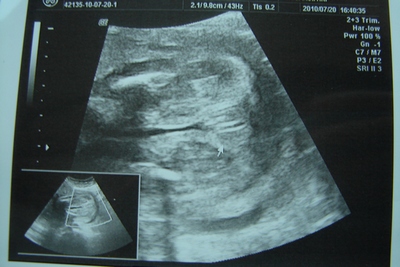

Rabbe: kaptam képet, de nem nagyon látszódik rajta, nem sikerült jó képet csinálnia a dokinőnek, mert a végén már megunta a leskelődést és hátat fordított.